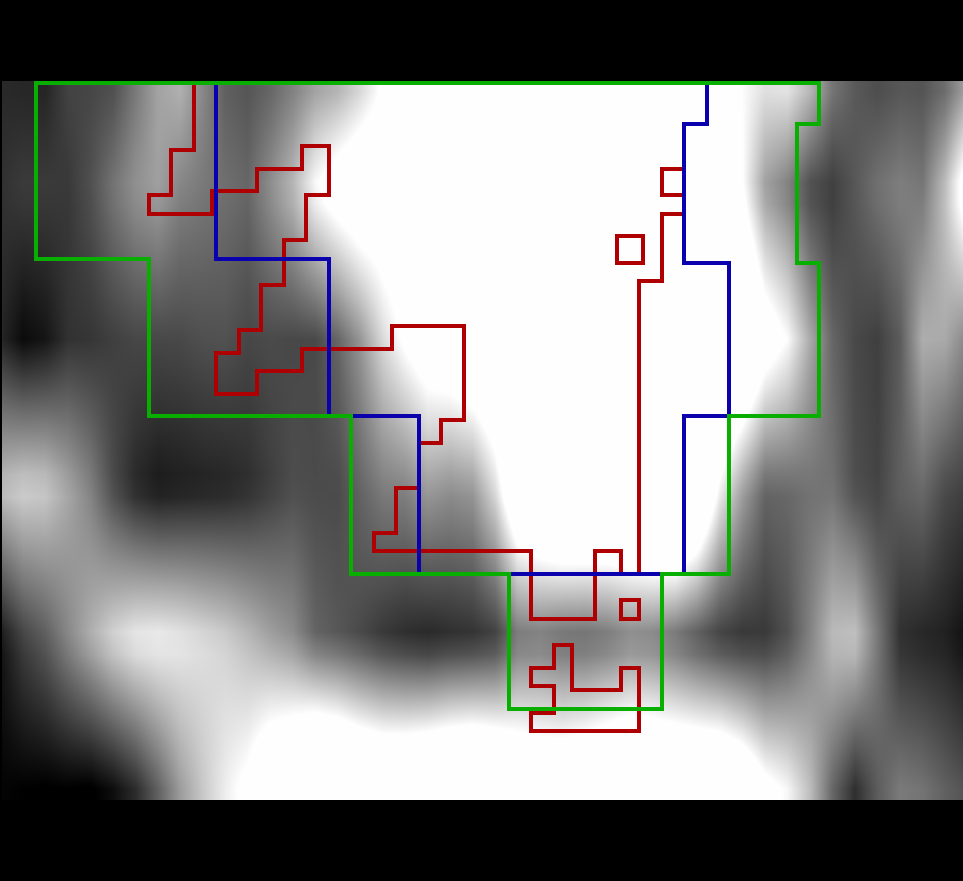

a) DirLab08 deformation grid

for inhale to exhale registration

a) DirLab08 deformation grid

for inhale to exhale registration

b) DirLab08 with overlayed image foldings

(Jacobi determinant 0)

b) DirLab08 with overlayed image foldings

(Jacobi determinant 0)

c) DirLab08 registration error

c) DirLab08 registration error

d) SC-N-3 deformation grid

for diastolic to systolic registration

d) SC-N-3 deformation grid

for diastolic to systolic registration

e) SC-N-3 with overlayed image foldings

(Jacobi determinant 0)

e) SC-N-3 with overlayed image foldings

(Jacobi determinant 0)

f) SC-N-3 contours (green: input,

blue: target, red: result)

f) SC-N-3 contours (green: input,

blue: target, red: result)